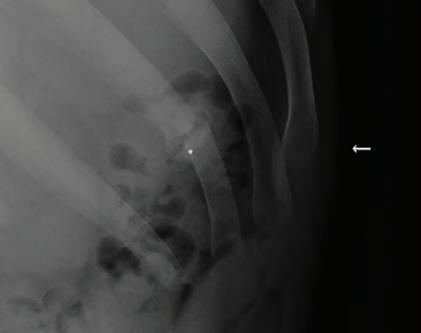

Sir Charles Gairdner Hospital houses WA’s adult CF centre, with a multidisciplinary team including CF doctors, nurses, physiotherapists, dieticians, pharmacists and a social worker. It also liaises with the paediatric CF team at Perth Children’s Hospital, helping patients transition to the adult unit.

Mr Messer said it needed to be able to provide comprehensive care to meet the complex healthcare needs of adults with CF.

“The treatment model is shifting, and we’re talking to the State Government to say that we need to ensure the facility that provides

that outpatient care, the CF clinic, is actually fit for purpose,” he said.

“It was developed in the 1990s and the number of people with CF going to the hospital was about 100, whereas we now have well over 200 people with CF going there.

“But it hasn’t really kept pace, so it’s not up to standard and we’re saying you will lose the benefits that have been achieved if we don’t keep the standards and services, and we don’t have that in WA.

“That will require extra funding. If you don’t provide good care there’s no point in providing people with new drugs because they will end up being unwell because they couldn’t get access to an appropriate facility, and then the only way is to go into hospital as an in-patient which is much more expensive.”